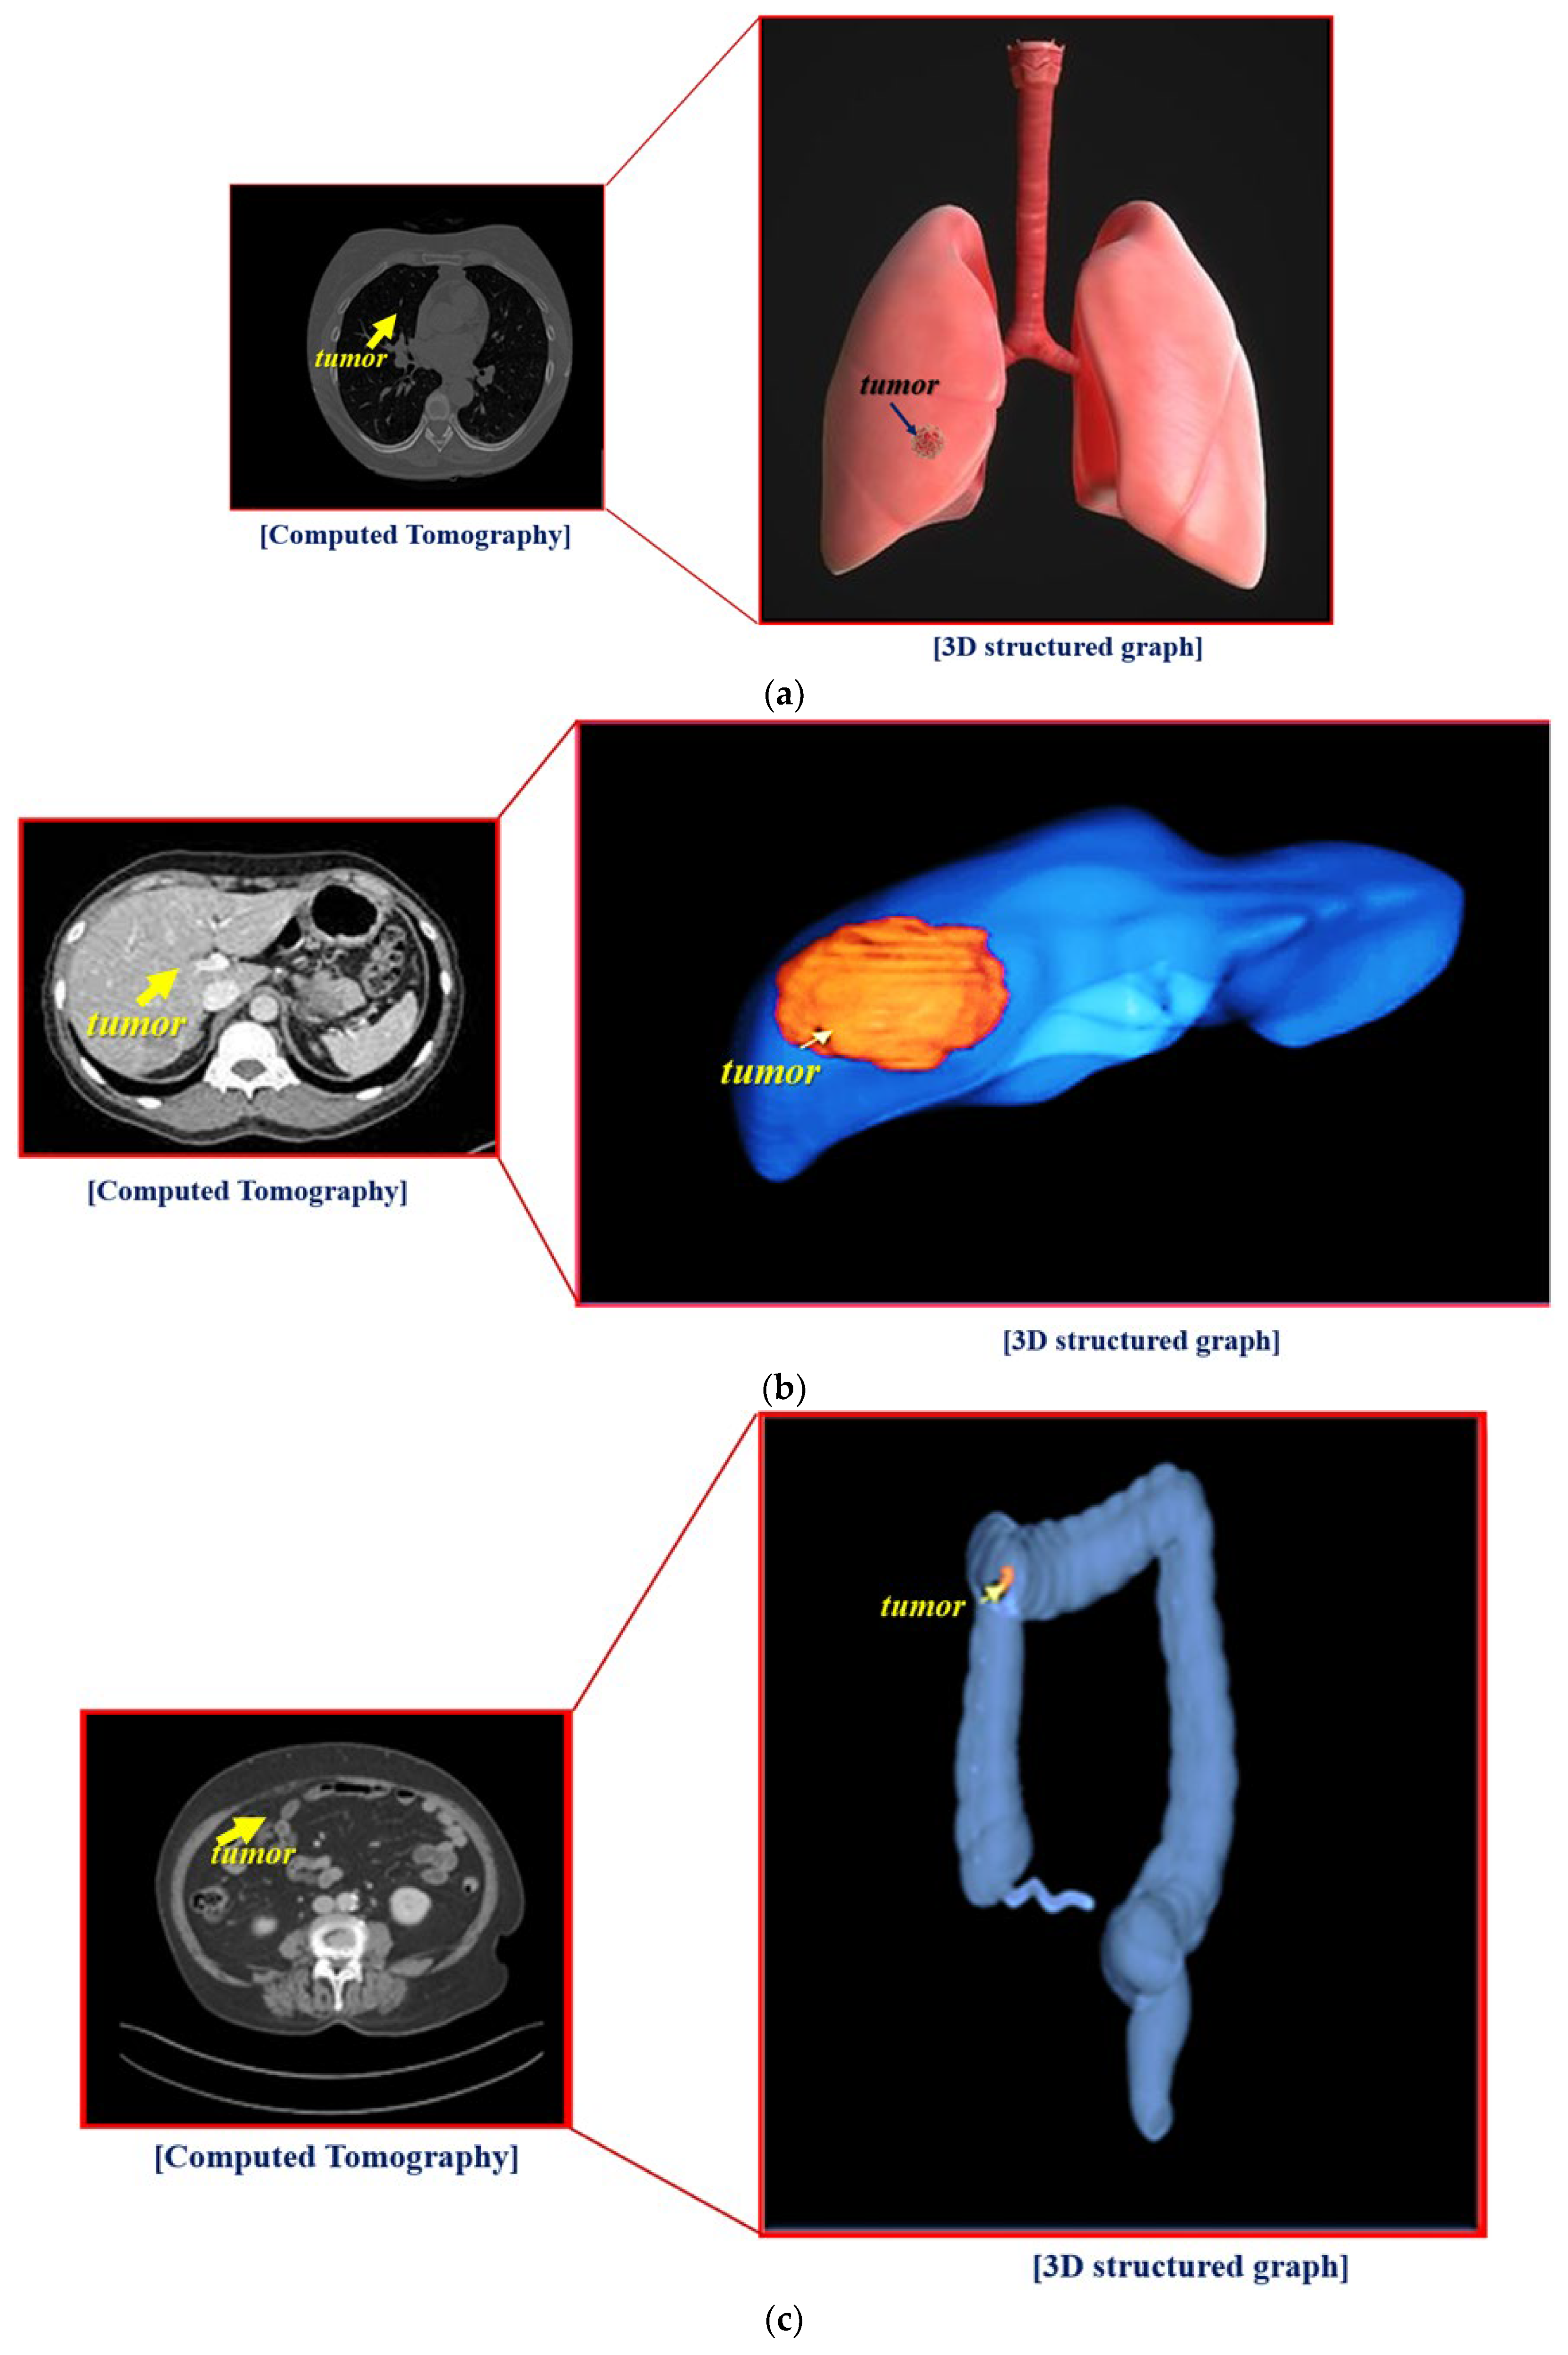

An HDMI cable connects the hologram with the laptop, and Wi-Fi connection is also available. However, for security reasons, a wired connection is recommended. In addition, the notebook is connected to a Picture Archiving and Communication System (PACS) server and can provide computed tomography (CT) or magnetic resonance imaging (MRI) images of tissues (for example, lungs, liver, colon, stomach, and brain) as shown in Figure 6. Video can be shown both in Windows and Linux environments. However, for general use, the window preferences may be appropriate. The overall picture of the holographic system was taken during the hologram experiment.

The overall size of the hologram system is 6.15 × 26.0 × 39.0 cm3, and the fabricated hologram system is shown in Figure 9. The imaging files of the lungs, liver, and colon can be obtained using the collection of medical servers with PACS tools thought the department of radiology by Gachon University Gil Medical Center in Korea.

As shown in Figure 9, the images of the lungs, liver, and colon are used for a CT program. Thus, the CT images of organs can be sent to the laptop and transmitted to the hologram system.

Therefore, to test the reliability and feasibility of the hologram program, imaging of the organs (large intestine, liver, and lungs), as shown in Figure 10. The images were taken using an external camera simultaneously with visual observation.

From the figure, the S-colon and the appendix, ascending colon, descending colon, and transverse colon are clearly observed in the colon, and the left- and right-side lobes are clearly visible in the liver. Hologram images of colon, liver, and lung were reproduced 3 times to obtain results for reliability verification. The results obtained through three replays showed a slight difference in resolution, but mostly the same results were obtained. The lung hologram also provides clear left and right observations to assist healthcare professionals with easy visualization when training patients or with instantly observing the state of a disease in an operating room.

Figure 6. Test results obtained using the proposed hologram system: (a) Lung, (b) Liver, and (c) Colon.

Figure 10. Realization of the imaging test using the proposed hologram system.